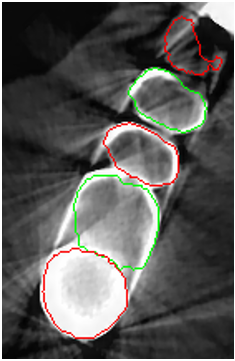

Despite all the appealing features from the contour propagating scheme, level-set methods demonstrate a common limitation, i.e., it is difficult to delineate unclear boundaries (Fig. 2). In a CBCT, the boundaries between the tooth root and the alveolar bone have weak edge characteristics (i.e., a low magnitude of gradient; Fig. 2a) and the presence of severe metal artifacts (Fig. 2b), which hinder the accurate propagation of a contour-based level-set method. Furthermore, level-set methods require tedious manual user interaction to define the initial contour [4, 5, 7], indicating a semiautomated algorithm.

The manual seeded level-set methods [6, 7] demonstrate inferior performances while segmenting teeth with predominant metal artifacts (Table II). The energy-based (i.e., level-set function) algorithmic approach failed while defining an optimum stopping criterion (Fig. 12b). The AJI measures for level-set methods are omitted because the box detectors do not exist in the level-set-based methods. In particular, the low precision and sensitivity values indicate that level-set methods have over-segmented or under-segmented the teeth in many cases (Figs. 12b and 13a). The accuracies of the Mask-RCNN [17] and ToothNet [11] showed comparable performance to the level-set-based methods. The instance segmentation framework successfully detected and segmented the teeth automatically. However, it failed to detect all the teeth regions accurately, which resulted in a degradation of the segmentation performance. Moreover, the performance of the segmentation itself also showed low accuracy owing to the metal artifacts (Figs. 12c and 12d). Figure 13 illustrates the more severe conditions of metal artifacts. The performance of the detection and segmentation processes significantly degraded in ToothNet [11] (Fig. 13b) and Mask-RCNN [17] (Fig. 13c). Conversely, our proposed method outperformed the other state-of-the-art methods (Figs. 12e and 13d); further, the comparison between the PA- and non-PA-based results also demonstrated that the employment of a PA detector significantly improved the proposed architecture (Table II). The superior AJI value clearly shows that successful detection improved the overall performance.